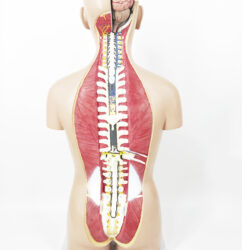

ATL-11 MALE MUSCLES FIGURE INTERNAL ORGANS HARD

The model is an anatomically accurate representation of the human anatomy, complete with superficial and deep musculature, the digestive system, lymphatic system, respiratory system, urinary system, circulatory system, endocrine system, and nervous system. Our model has removable organs and dissectible features for a complete educational experience.

Classification: